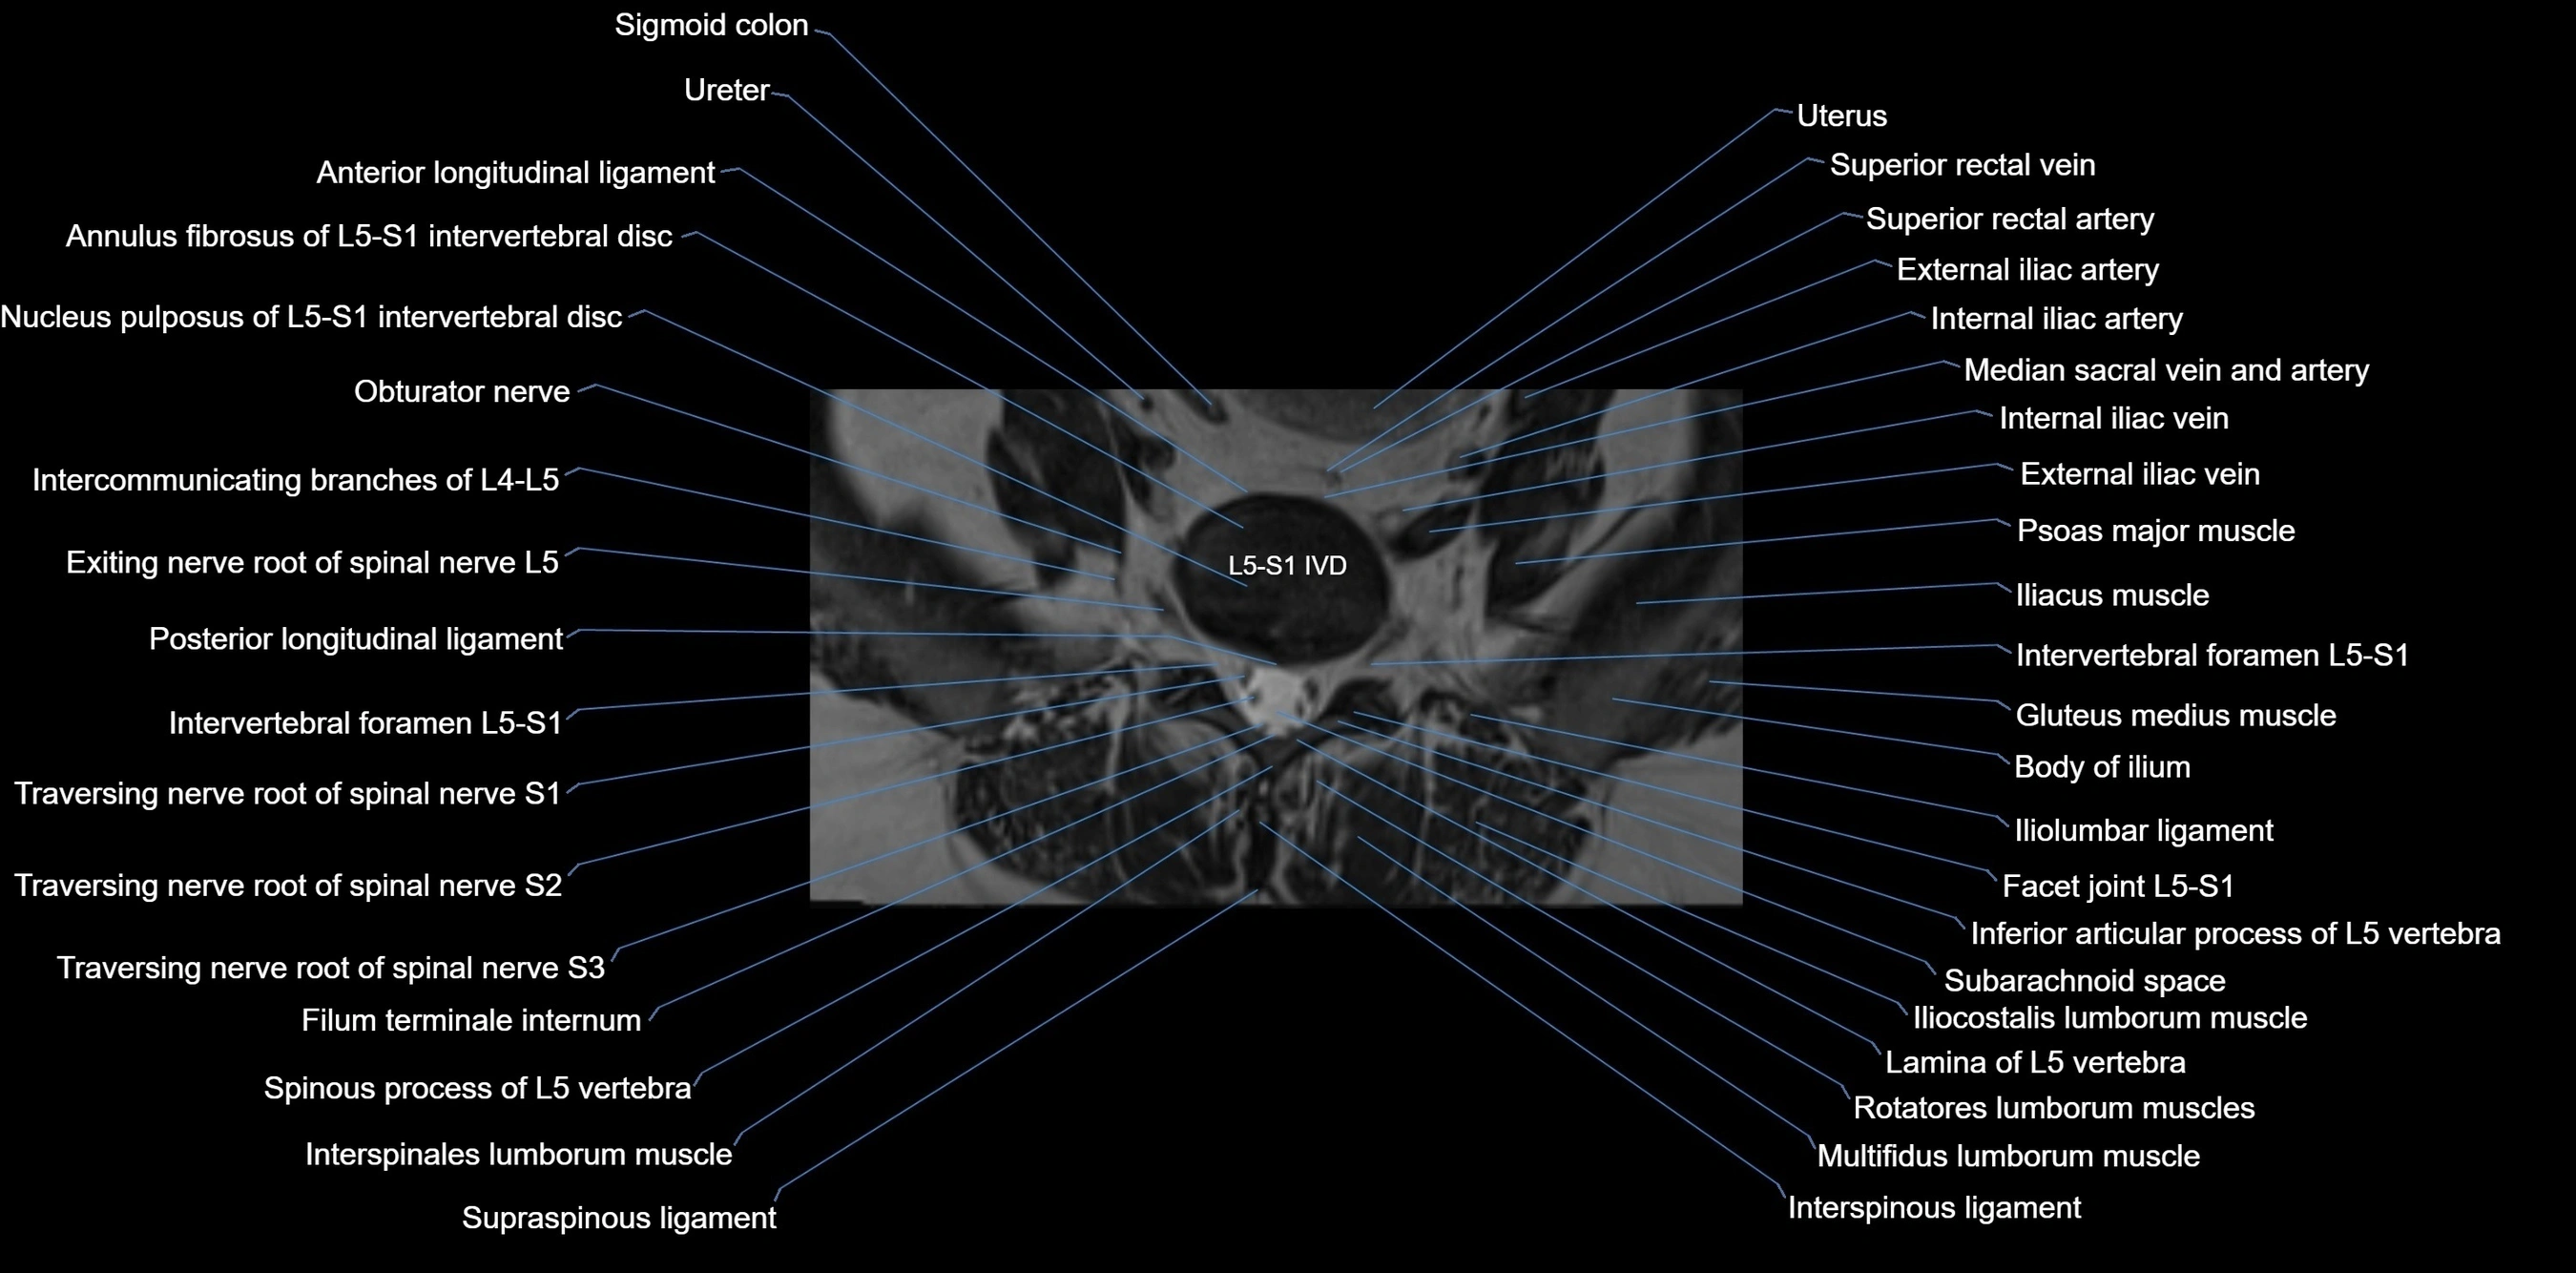

MRI Appearance

T1-weighted images:

• Cortical bone appears very low signal (dark); marrow shows intermediate signal

• Iliac fossa fat is bright against low-signal cortex

T2-weighted images:

• Cortical bone remains dark

• Marrow signal varies depending on fat content; edema or tumor shows hyperintensity

STIR:

• Suppresses fat, making bone marrow edema, fractures, or infiltrative lesions appear bright

• Excellent for trauma, sacroiliitis, and metastatic evaluation

T1 Fat-Saturated (Pre-contrast):

• Marrow: intermediate signal, fat suppressed

• Useful for detecting subtle marrow abnormalities adjacent to iliac cortex

T1 Fat-Saturated Post-Contrast (Gadolinium):

• Enhances vascularized structures, marrow pathology, tumors, and inflammatory changes

• Highlights soft tissue or bone invasion in pelvic neoplasms

MRI Non-Contrast 3D Imaging:

• Provides 3D morphology of iliac wing, crest, and articulations

• Used in preoperative planning for pelvic surgery and trauma reconstruction

CT image

image